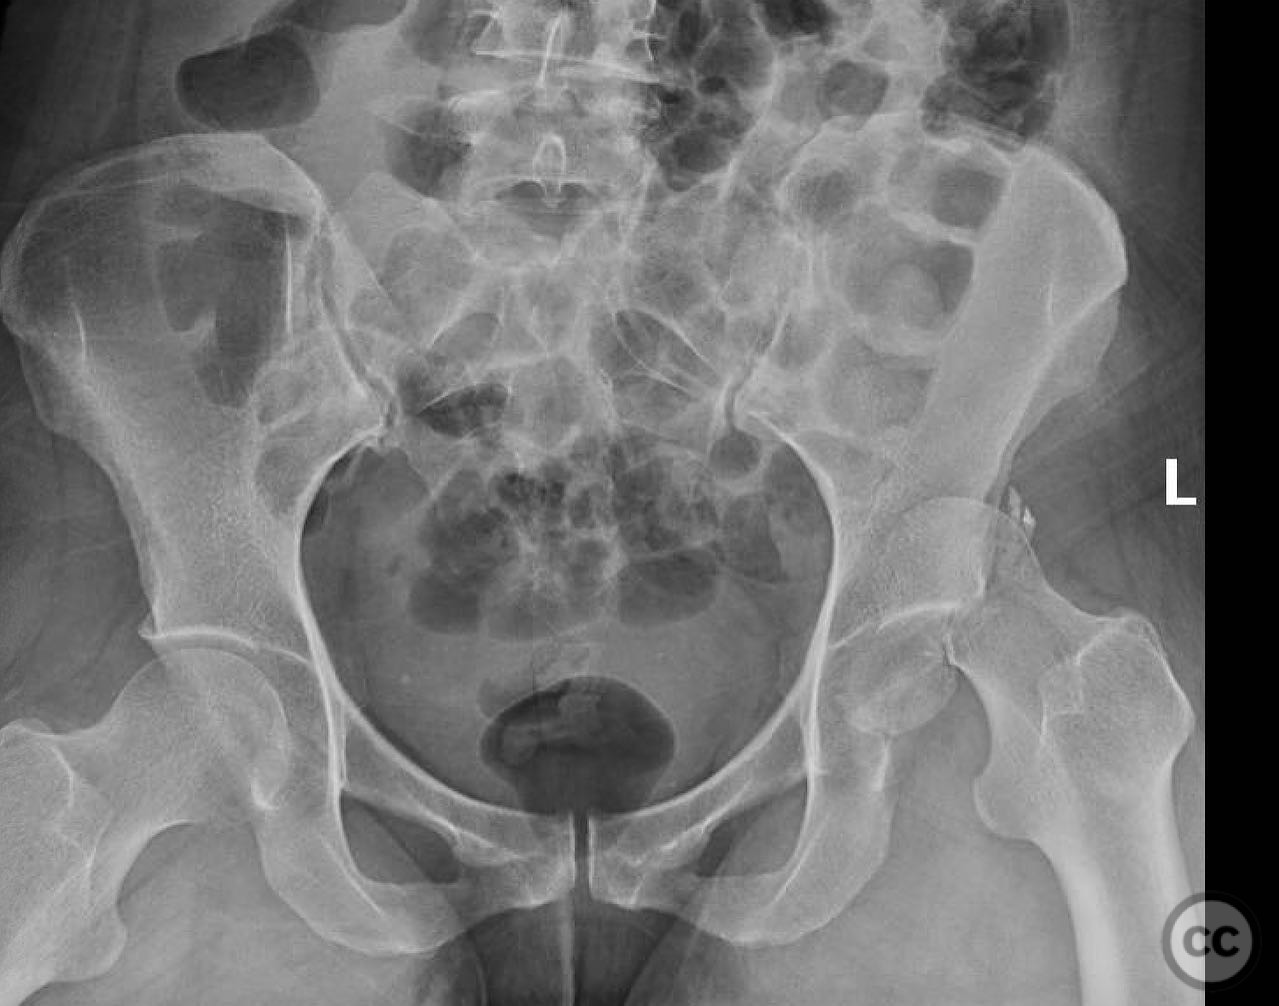

Clinical and radiological findings:  A 33-year-old female involved in a motor vehicle collision presented with a posterior hip dislocation accompanied by a comminuted supra-foveal femoral head fracture, a cranial peripheral posterior wall fracture, and a non-displaced femoral neck fracture. The injury is associated with a risk of sciatic nerve palsy and avascular necrosis (AVN).

Patient positioning:  The patient was positioned in the lateral decubitus position to facilitate the Gibson approach and anterior dislocation of the hip.